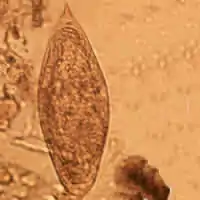

Schistosoma mansoni egg

Schistosoma mansoni